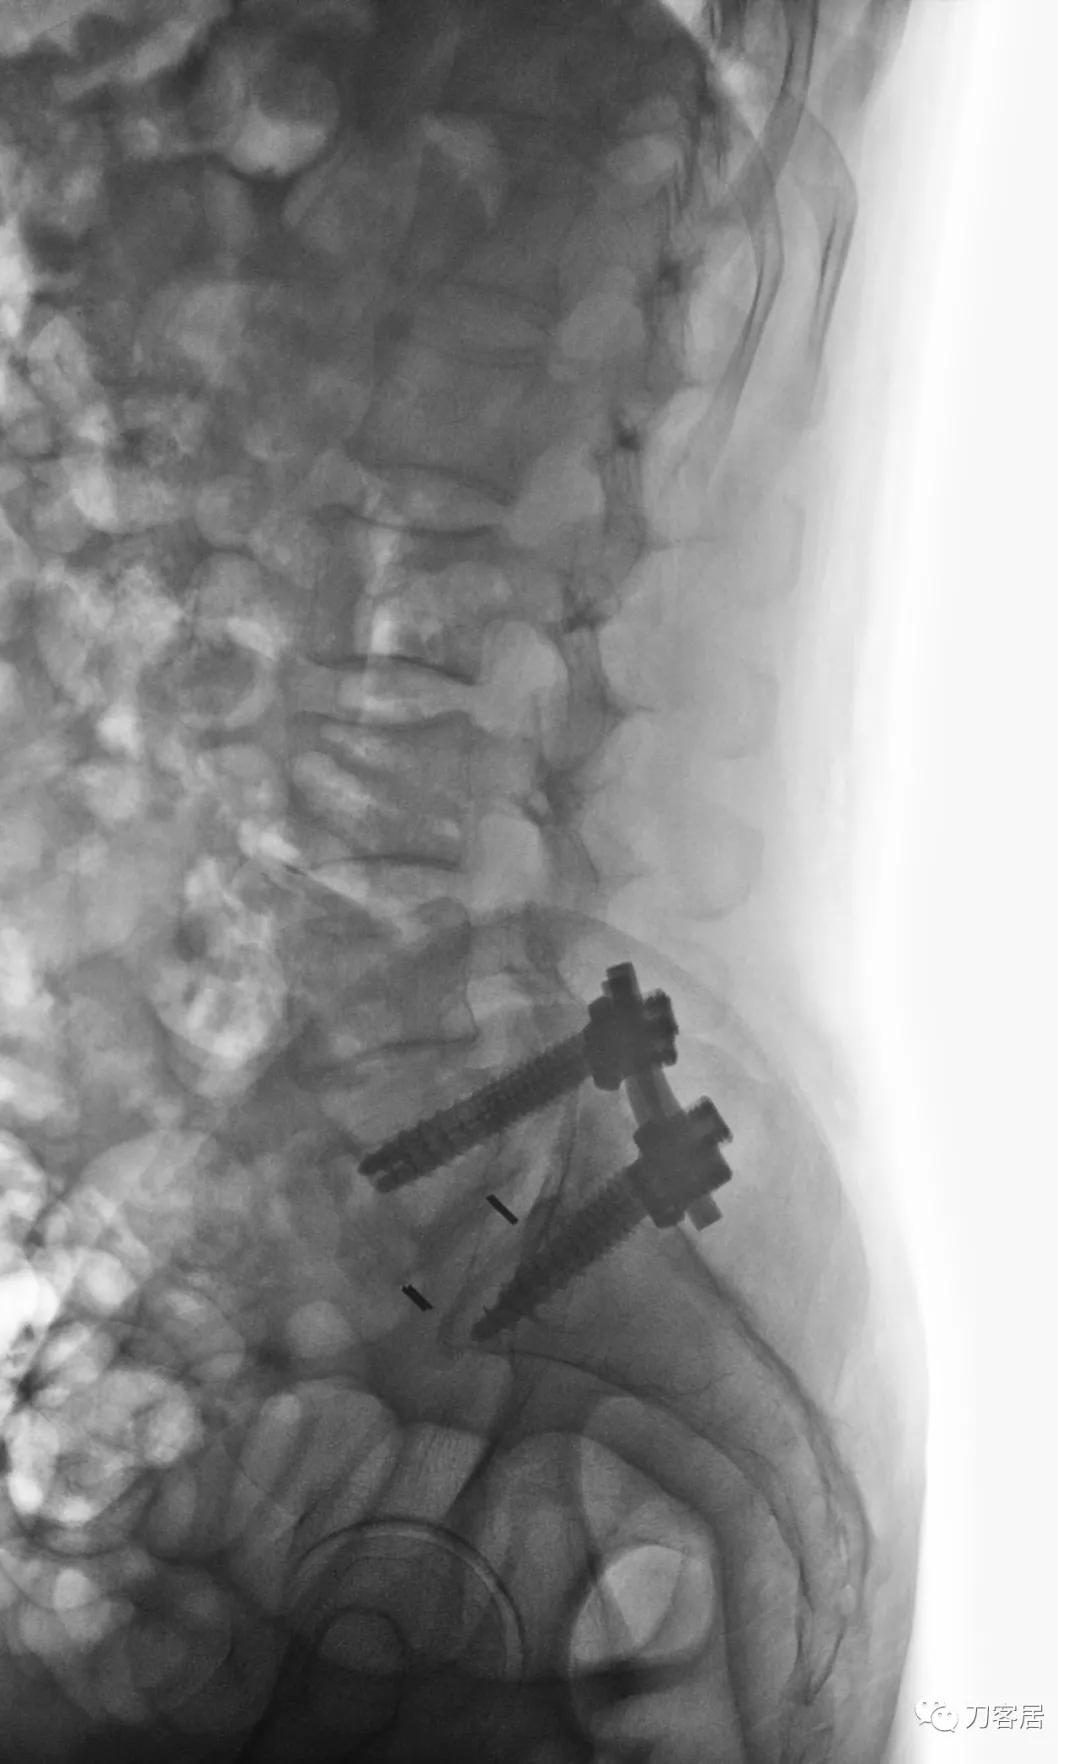

手术名称:可扩张通道辅助下径腰椎肌间隙(Wiltse)入路腰5骶1椎板切除减压,椎间盘切除,腰5滑脱复位,植骨融合内固定术。

图15. 20210701术后腰椎正侧位X线片

图17. 20210701术后腰椎侧位X线片

手术后原有症状缓解。患者同时有骨质疏松症,骨密度-3.1, 住院期间同时予以抗骨质疏松症治疗。高中同学反馈,患者回家后症状明显缓解,心情也好转。